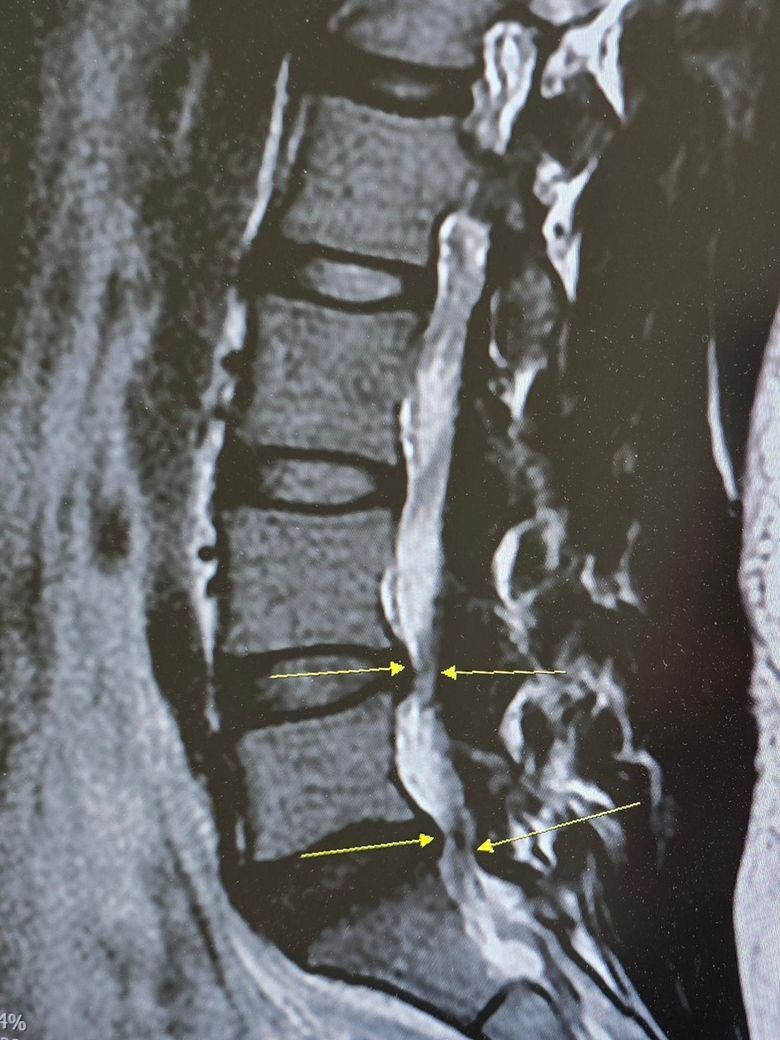

동네병원가서 찍은 요추mri인데 4,5번이 퇴행성변형을 동반하면서 튀어나왔다며 신경성형술을 권하시더라구요.. 20대 중반에서 볼 수 있는 허리는 아니라구요🥺 근데 좀 무서워서 일단 생각해보겠다고 말씀드리고 왔습니다ㅠ

일단 지금은 허리, 골반쪽, 엉덩이-허벅지 이어지는 부분, 허벅지 앞쪽, 무릎, 엄지발가락(무지외반증때문인지 디스크 때문인지 모르겠음)에 통증이 있고 다리는 약간 저린 불편감?(스타킹 오래 신었다가 벗었을때 같은)이 있습니다.

허리 통증은 머리감을때 숙이는게 아예 안되는건 아니지만 한쪽 팔꿈치를 허벅지에 지탱하면 감을수있는 정도에요. 서있다가 의자에 앉으면 허리가 눌리는것 같이 아파서 살짝 일어났다가 살살 다시 앉아요.